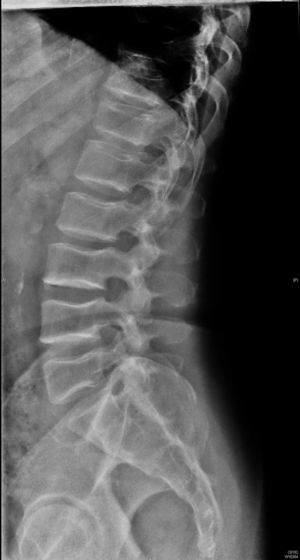

Caso clínicoVarón de 59 años con antecedente personal de diabetes mellitus tipo 2 en tratamiento con antidiabéticos orales, que acude a consulta de Reumatología por dolor inguinal bilateral y dorsolumbalgia de intensidad dolorosa progresiva, ambos de ritmo mecánico, que el paciente califica de muy intenso y que desencadenan dificultad progresiva para la deambulación; y por episodios de disnea de moderados esfuerzos, cuyo origen, estudiado por Neumología, era debido a dificultades en la expansión torácica. El cuadro doloroso no había presentado una respuesta satisfactoria a antiinflamatorios no esteroideos ni a opiáceos menores. En la exploración física se observa talla de 146cm, marcada cifosis dorsal, obesidad troncular, limitación importante para la flexoextensión y las rotaciones de ambas articulaciones coxofemorales, y braquidactilia en ambas manos. Hemograma y bioquímica sanguínea con valores normales. El estudio radiológico convencional de columna dorsolumbar, anteroposterior de pelvis y posteroanterior de manos se muestran en las figuras 1 a 4.

El paciente descrito presenta datos que sugieren una displasia espondiloepifisiaria tarda. Esta entidad tiene una herencia recesiva ligada al cromosoma X1, estando por lo tanto afectados sólo los varones. Se han descrito mutaciones en el gen SELD en el cromosoma Xp22.12-p 23.311. El diagnóstico se realiza entre los 5 y los 10 años de edad, cursando con enanismo de tronco corto; esto es, retraso en el crecimiento de la columna vertebral con una talla media final de 145cm y desproporción entre la longitud de las extremidades y el tronco2,3. La articulación coxofemoral está siempre afectada en coxa vara con aplanamiento leve de las epífisis, que conducen a cambios artrósicos precoces, y que pueden, en estadios más avanzados, incapacitar al paciente2–4. A nivel axial se describen cambios displásicos vertebrales con platiespondilia, que provocan cifosis progresiva4–6 con aumento del diámetro anteroposterior del tórax, y que en último término puede provocar episodios de disnea. No aparece retraso mental, se han descrito formas familiares con asociación a condrocalcinosis7,8 y existe una forma de displasia espondiloepifisiaria tarda asociada a artropatía degenerativa precoz, que puede simular artritis reumatoide juvenil9.